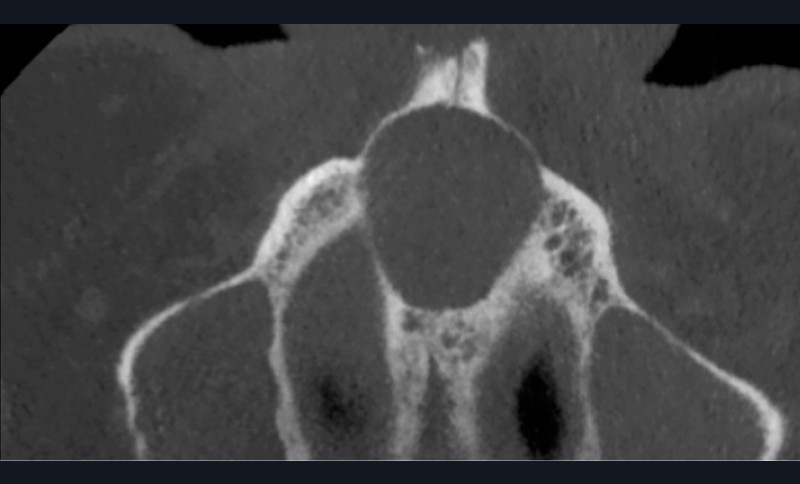

- Plus rarement, extension latérale jusqu’aux prémolaires de façon asymétrique (fig. 5).